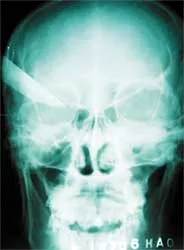

Vết dao đâm - hình chụp qua phim.

Kết quả chụp X quang cho thấy vết đâm (vào thái dương phải) sâu 5cm, qua não hơn 3cm. Bệnh nhân được mổ ngay và sau hơn hai giờ đồng hồ, con dao được lấy ra khỏi đầu bệnh nhân an toàn.